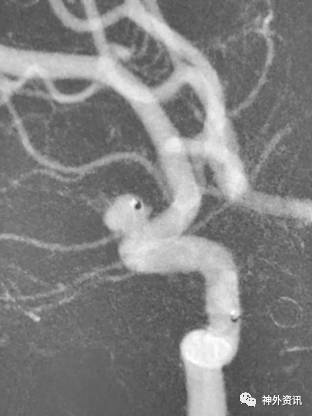

大C塑形

10mm以上的大动脉瘤:

(1)C型头端完全进入动脉瘤囊内,微导管的盘旋有利于均匀填塞

(2)避免微导管头端过早踢出

病例一